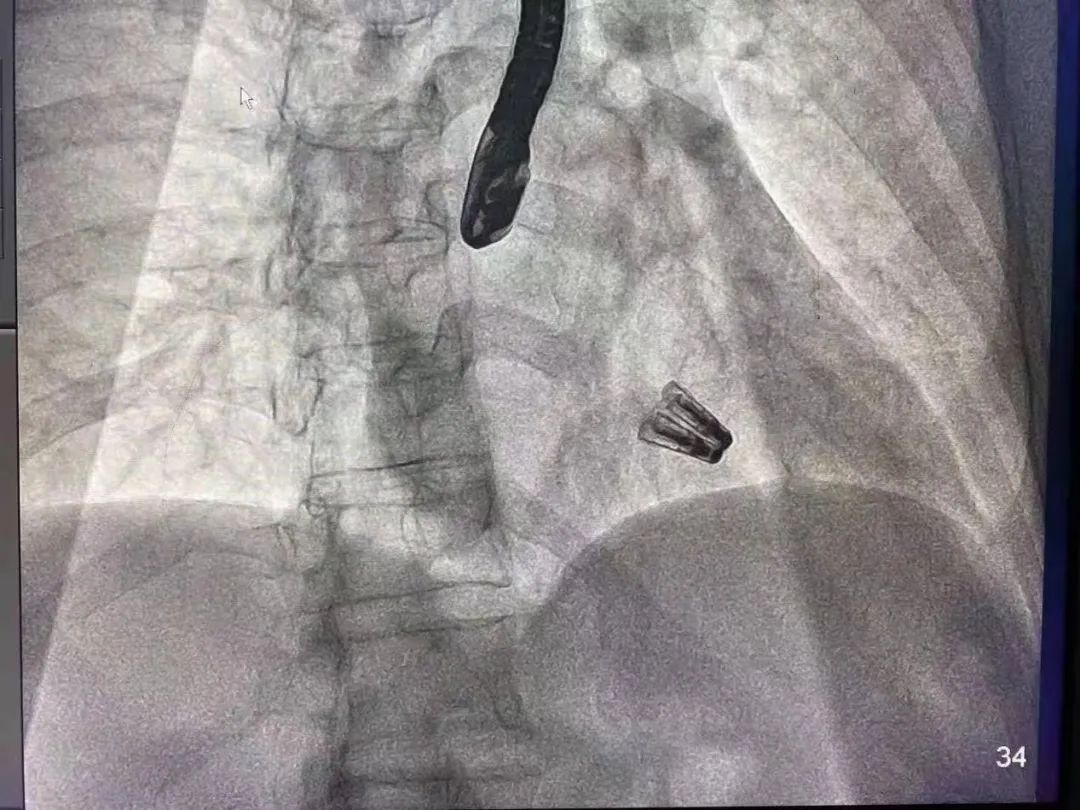

DragonFly瓣膜夹释放

在麻醉和体外循环团队保驾护航下,器械经股静脉穿刺房间隔,通过输送系统送入患者左心房,到达二尖瓣膜反流处,在经食道超声及DSA引导下,术者通过反复评估二尖瓣膜脱垂范围、抓捕位置、反流程度,精准夹合,成功植入两枚DragonFly瓣膜夹。